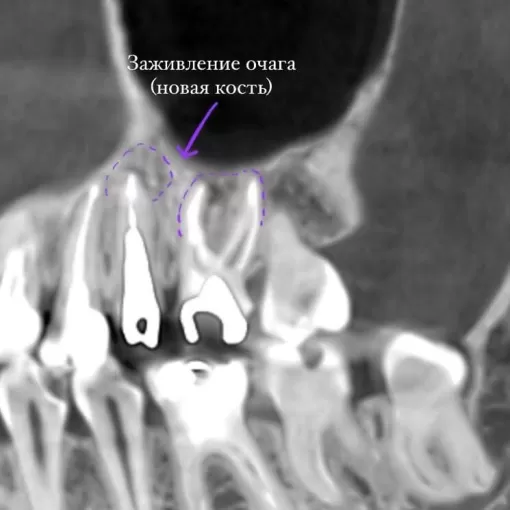

Клинический случай лечения "кисты" зуба 4.7

Стоматолог-терапевт Петрусенко О.А.

Пациент обратился с целью имплантации в области отсутствующего зуба 4.6. Однако после КЛКТ (3Д) исследования был обнаружен воспалительный процесс (киста) в области соседнего зуба 4.7 (рис. 1).